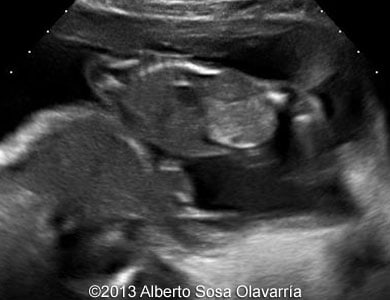

πŸ“ƒ Partial molar pregnancy thefetus.net

molar partial pregnancy

πŸ“ƒ Partial Molar Pregnancy

molar partial embedded